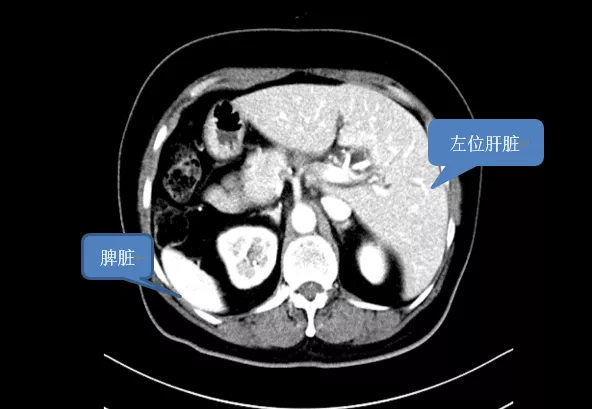

“鏡面人”,即內臟全反位的俗稱,心、肝、脾、肺、腎等器官的位置跟正常人完全相反,恰如人在鏡子中的影像一般,是一種罕見的先天性解剖變異,發生率僅為0.01%。

近兩月以來,患者王女士(化名)在無明顯誘因下出現面板、鞏膜黃染,左上腹陣發性疼痛,偶有劍突下隱痛及腹脹不適,伴有面板瘙癢、乏力等症狀,且病情逐漸加重。當地醫院檢查結果顯示,王女士是一名“鏡面人”,還患上了膽總管下段高分化腺癌。

餘水平教授詳細詢問病史,檢視影像學資料後,立即敏銳意識到,這是一個極為罕見的“鏡面人”合併膽總管下段惡性腫瘤的病例。經仔細評估,餘水平教授考慮可行機器人輔助下胰十二指腸切除術,遂收住我院。